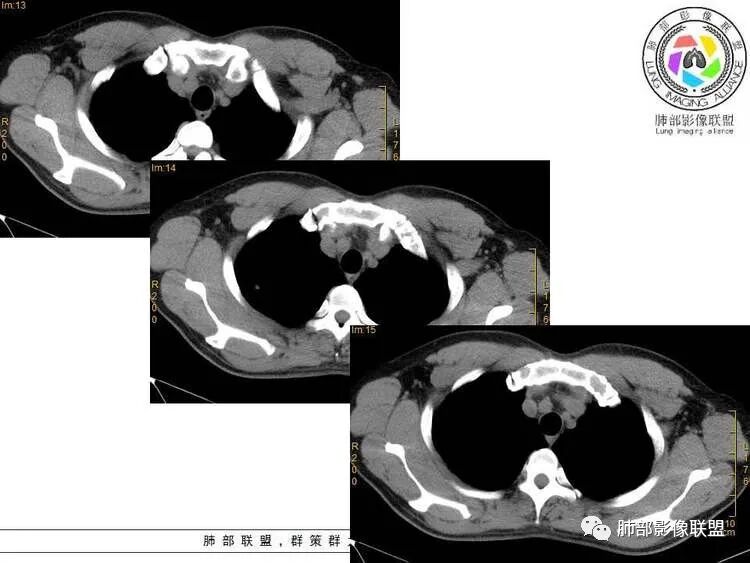

5.肺门及纵隔未见增大淋巴结。

1.胸膜下不规则结节影,相对单发和或局限,略散,呈三角形,星芒状长条索,周围细小结节,胸膜增厚黏连。继发性肺结核可能性是最大的!尤其是缺乏其他(如肺炎)相关病史。